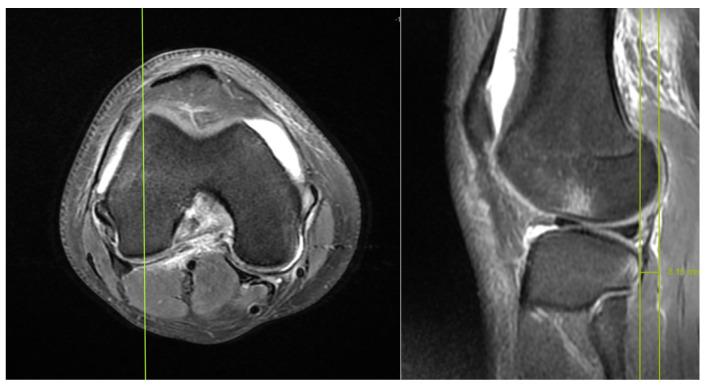

The aim of this study was to evaluate the presence of residual instability in the knee after ACL reconstruction through the analysis of MRI findings. This study included patients who underwent isolated ACL reconstruction between December 2019 and December 2021, and had preoperative and postoperative MRI, clinical scores, and postoperative isokinetic measurements. The anterior tibial translation (ATT) distance, coronal lateral collateral ligament (LCL) sign, and femorotibial rotation (FTR) angle were compared preoperatively and postoperatively. The correlation between the changes in preoperative-postoperative measurements and postoperative measurements with clinical scores and isokinetic measurements was examined. The clinical outcomes were compared based on the presence of a postoperative coronal LCL sign. Inclusion criteria were set as follows: the time between the ACL rupture and surgery being 6 months, availability of preoperative and postoperative clinical scores, and objective determination of muscle strength using isokinetic dynamometer device measurements. Patients with a history of previous knee surgery, additional ligament injuries other than the ACL, evidence of osteoarthritis on direct radiographs, cartilage injuries lower limb deformities, and contralateral knee injuries were excluded from this study. This study included 32 patients. After ACL reconstruction, there were no significant changes in the ATT distance (preoperatively: 6.5 ± 3.9 mm, postoperatively: 5.7 ± 3.2 mm) and FTR angle (preoperatively: 5.4° ± 2.9, postoperatively: 5.2° ± 3.5) compared to the preoperative measurements ( > 0.05). The clinical measurements were compared based on the presence of a postoperative coronal LCL sign (observed in 17 patients, not observed in 15 patients), and no significant differences were found for all parameters ( > 0.05). There were no observed correlations between postoperative FTR angle, postoperative ATT distance, FTR angle change, and ATT distance change values with postoperative clinical scores ( > 0.05). Significant correlations were observed between the high strength ratios generated at an angular velocity of 60° and a parameters FTR angle and ATT distance (-values: 0.028, 0.019, and r-values: -0.389, -0.413, respectively). Despite undergoing ACL reconstruction, no significant changes were observed in the indirect MRI findings (ATT distance, coronal LCL sign, and FTR angle). These results suggest that postoperative residual tibiofemoral rotation and tibial anterior translation may persist; however, they do not seem to have a direct impact on clinical scores. Furthermore, the increase in tibial translation and rotation could potentially negatively affect the flexion torque compared to the extension torque in movements requiring high torque at low angular velocities.

本研究旨在通过 MRI 检查结果分析评估 ACL 重建后膝关节的残余不稳定情况。本研究纳入了 2019 年 12 月至 2021 年 12 月期间接受单纯 ACL 重建的患者,且患者术前、术后均行 MRI、临床评分和术后等速测量。比较术前和术后胫骨前移(ATT)距离、冠状外侧副韧带(LCL)征和股骨胫骨旋转(FTR)角度。检查术前-术后测量值与术后临床评分和等速测量值之间的变化相关性。根据术后冠状 LCL 征的存在比较临床结果。纳入标准如下:ACL 破裂至手术的时间为 6 个月,术前、术后临床评分可用,使用等速测力计设备测量客观确定肌肉力量。排除既往膝关节手术史、除 ACL 以外的其他韧带损伤、直接 X 线片上骨关节炎证据、软骨损伤、下肢畸形和对侧膝关节损伤的患者。本研究共纳入 32 例患者。ACL 重建后,ATT 距离(术前:6.5 ± 3.9mm,术后:5.7 ± 3.2mm)和 FTR 角度(术前:5.4°±2.9°,术后:5.2°±3.5°)与术前测量值相比无显著变化(>0.05)。根据术后冠状 LCL 征的存在比较临床测量值(观察到 17 例,未观察到 15 例),所有参数均无显著差异(>0.05)。术后 FTR 角度、术后 ATT 距离、FTR 角度变化和 ATT 距离变化值与术后临床评分之间无观察到相关性(>0.05)。在角速度为 60°时产生的高力量比与 FTR 角度和 ATT 距离参数呈显著相关性(-值:0.028、0.019,r 值:-0.389、-0.413)。尽管进行了 ACL 重建,但间接 MRI 检查结果(ATT 距离、冠状 LCL 征和 FTR 角度)未见明显变化。这些结果表明,术后胫骨股骨旋转和胫骨前移可能持续存在,但它们似乎对临床评分没有直接影响。此外,与伸展扭矩相比,在需要低角速度高扭矩的运动中,胫骨平移和旋转的增加可能对屈曲扭矩产生负面影响。